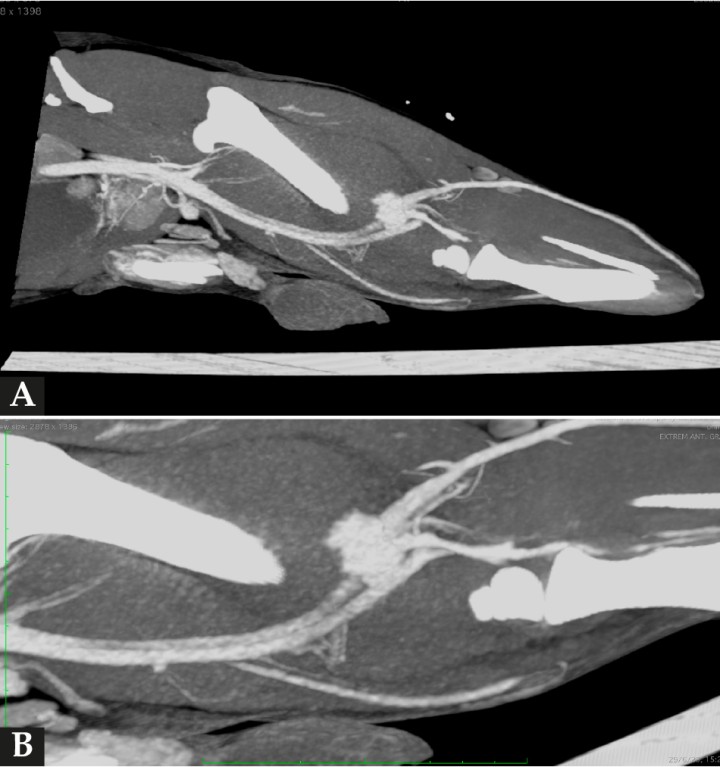

En los tejidos blandos junto al aspecto caudodistal del fémur, se visualizó una estructura redondeada, de 3 cm de diámetro y de atenuación líquido/tejido blando en precontraste, con un realce marcado postcontraste sugestivo de estructura vascular (Figs. 2 y 3). La vena y arteria femoral derecha presentaban apariencia normal hasta el aspecto distal del fémur, donde la vena femoral parecía conectar con la estructura descrita. La arteria femoral quedaba en íntimo contacto con dicha estructura, aunque no parecía estar conectada. Este hallazgo era compatible con una dilatación aneurismática afectando a la vena femoral. Distalmente a esta lesión, la arteria y vena poplíteas se observaban ligeramente más distendidas en comparación al lado contralateral. También había un leve aumento de atenuación de la grasa subcutánea de forma difusa distal a la lesión compatible con edema subcutáneo.

<p>(<strong>A</strong>) Imagen de TC en ventana tejidos blandos, tras la administración de contraste, reconstruida en plano sagital y MIP (proyección de máxima intensidad). Se observa una estructura redondeada con marcada captación de contraste caudal al fémur y caudodistal al defecto femoral. (<strong>B</strong>) Imagen de TC en ventana de tejidos blandos, tras la administración de contraste, reconstruida en plano sagital oblicuo y MIP. Detalle de la lesión descrita en (<strong>A</strong>) y de su relación con la vascularización regional.</p>

(A) Imagen de TC en ventana tejidos blandos, tras la administración de contraste, reconstruida en plano sagital y MIP (proyección de máxima intensidad). Se observa una estructura redondeada con marcada captación de contraste caudal al fémur y caudodistal al defecto femoral. (B) Imagen de TC en ventana de tejidos blandos, tras la administración de contraste, reconstruida en plano sagital oblicuo y MIP. Detalle de la lesión descrita en (A) y de su relación con la vascularización regional.